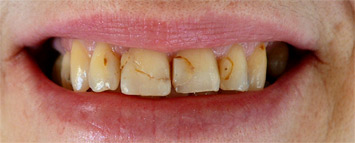

prije